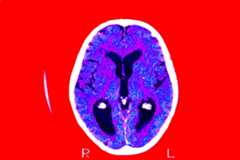

Empresas médicas